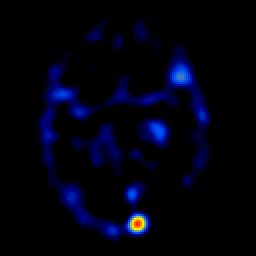

overlay -- Slice #12

[Home][Help][Clinical] Slice 12